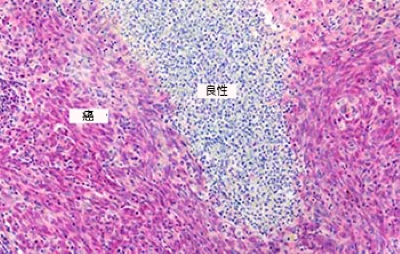

宫颈鳞状细胞癌–强HPV表达